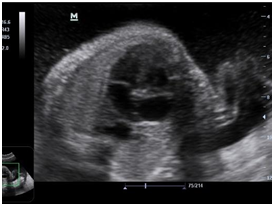

Newborn female was born at 37 weeks 5 days as a product of a second pregnancy, with prenatal diagnosis of duodenal atresia and esophageal stenosis (Figure 1). Due to a previous cesarean section and rupture of the membranes, an emergency caesarean section was performed. Birth weight was 2100 grams APGAR scores were 8–9 at…min. A thoracic-abdominal radiograph was performed, showing thorax without alterations and an image suggestive of duodenal atresia (Figure 2). An echocardiogram CIA 0.5, PCA: 0.2X0.3 showed mild dysplasia of aortic and pulmonary valves. Abdominal laparotomy at 24hours of life, revealed duodenal stenosis secondary to annular pancreas, intestinal malrotation and non-meconium plastic peritonitis without evidence of perforation. The defect was corrected by adhesiolysis, duodeno-duodenal anastomosis and incidental appendectomy.

Figure 2 Thoracic-abdominal radiography before corrective atresia surgery.